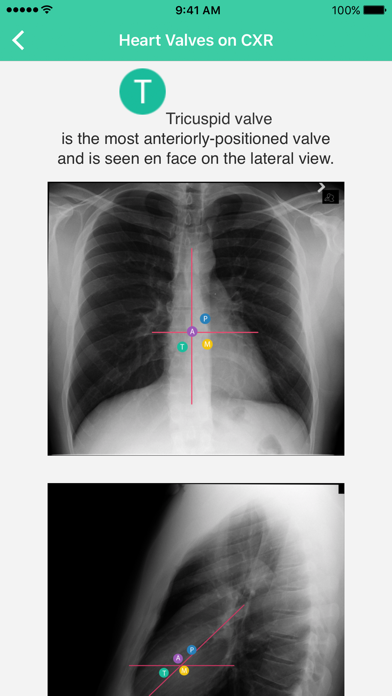

Radiology Toolbox Pro is designed by a practicing radiologist to help radiologists, radiology technologists, other health practitioners and students.